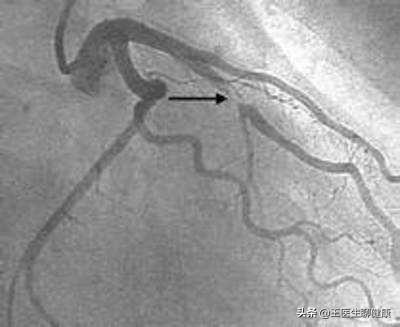

図に示すように、クリッピングされたヘッドマーク部分は約40%狭くなっている。